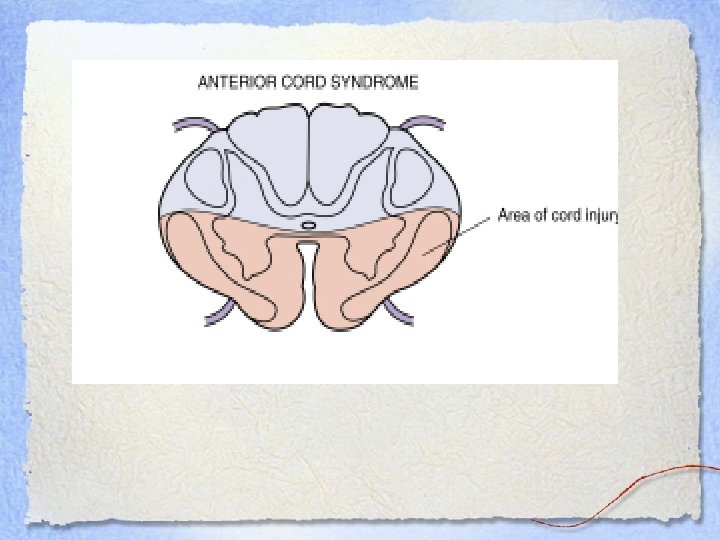

Anterior Cord Syndrome • Damage to the corticospinal and spinothalamic tracts • Dorsal column function is intact • Loss of: – Motor function – Pain and temperature sensation • Vibration, position and crude touch are maintained

Anterior Cord Syndrome • Damage to the corticospinal and spinothalamic tracts • Dorsal column function is intact • Loss of: – Motor function – Pain and temperature sensation • Vibration, position and crude touch are maintained